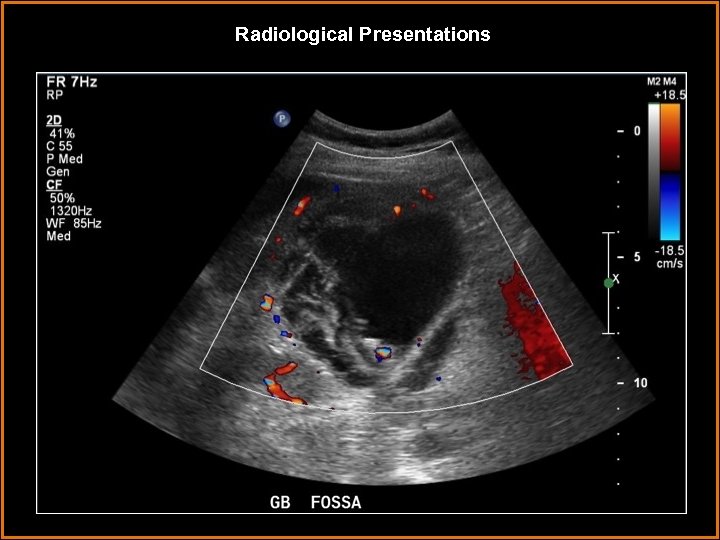

Findings and Differentials Findings: Striated thickening of the gallbladder wall with multiple hyperechoic, serpentine Findings and Differentials Findings: Striated thickening of the gallbladder wall with multiple hyperechoic, serpentine bands separated by hypoechoic areas. Also, intraluminal membranes concerning for desquamative mucosa. Differentials: • Acute cholecystitis – Wall thickening and pericholecystic fluid are neither sensitive nor specific. The most sensitive finding is a gallbladder stone with a positive Murphy’s sign. • Hydatid cyst – intrahepatic cystic lesion with floating membranes or multiseptated cysts. • Emphysematous cholecystitis – dirty shadowing from gas in gallbladder wall. • Volume overload – usually uniform, homogeneous wall thickening.

Discussion • Gangrenous cholecystitis is on the severe end of the spectrum of acute Discussion • Gangrenous cholecystitis is on the severe end of the spectrum of acute cholecystitis. • It is thought to be a result of tension in the gallbladder wall secondary to increased distention. This results in ischemic necrosis of the gallbladder wall, sometimes due to cystic artery thrombosis. • The condition occurs in older patients, usually male. Coexisting vascular disease is commonly seen. Sonographic Murphy’s sign is usually absent, thought to be due to devascularization and denervation. • On ultrasound, the primary finding is layered or striated gallbladder wall thickening. Usually, it is irregular with luminal projections. Less often seen, but more specific, are intraluminal membranes that are thought to represent desquamative mucosa.